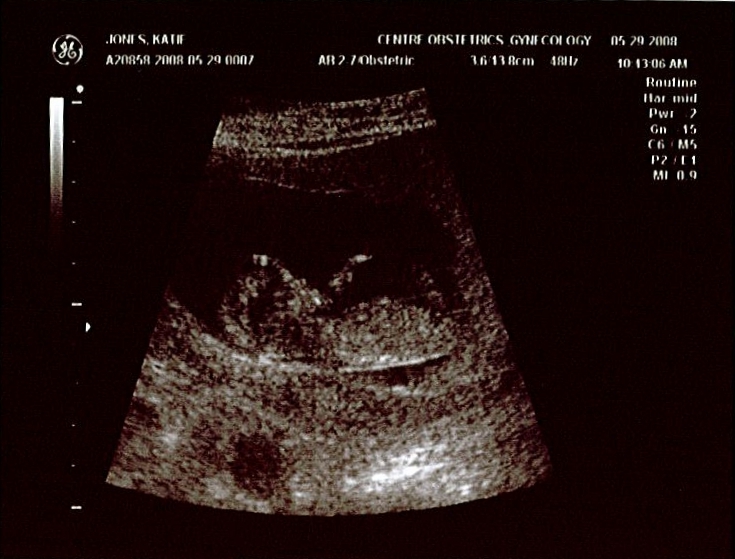

According to the ultrasound today (images are shown below), all systems are go for baby Jones. She/he has now surpassed six centimeters, so her/his length is about the same as the width of my iPhone. If you click on the first image posted below and view the larger image size, you’ll see that she/he already seems to have Katie’s nose. Katie has been feeling fairly good lately except for some nagging allergies.